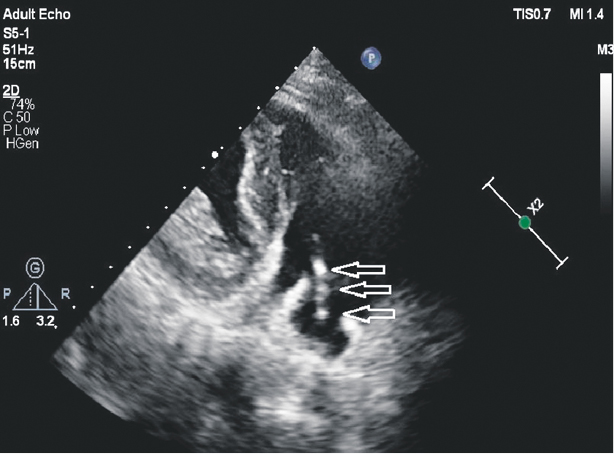

A month after discharge, fever recurred, and this time, in addition to the symptoms already listed earlier, there was hyperemia and soreness in the area of the pacemaker bed. In early December 2018, the patient was hospitalized with a diagnosis of “pacemaker bed abscess”. In control TTE and TEE, no reliable vegetation was found in the projection of electrodes, valves, and free endocardium. There was only uneven compaction and thickening of some areas of the electrode (Fig. 2). Staphylococcus Aureus was re-isolated in blood cultures. The therapy was carried out with vancomycin (1 g) with gentamicin (80 mg) for 25 days. After sanitation of the abscess and with antibiotic therapy, regression of all symptoms was again noted, with complete normalization of blood counts.

Fig. 2. Echocardiograms of patient A. Arrows indicate uneven compaction and thickening of the electrode sections located in the right chambers of the heart. Reliable formations in the projection of the electrodes are not determined. A — Four-chambered apical section; B — Modified three-chambered apical section (through the inflow sections of the right ventricle).